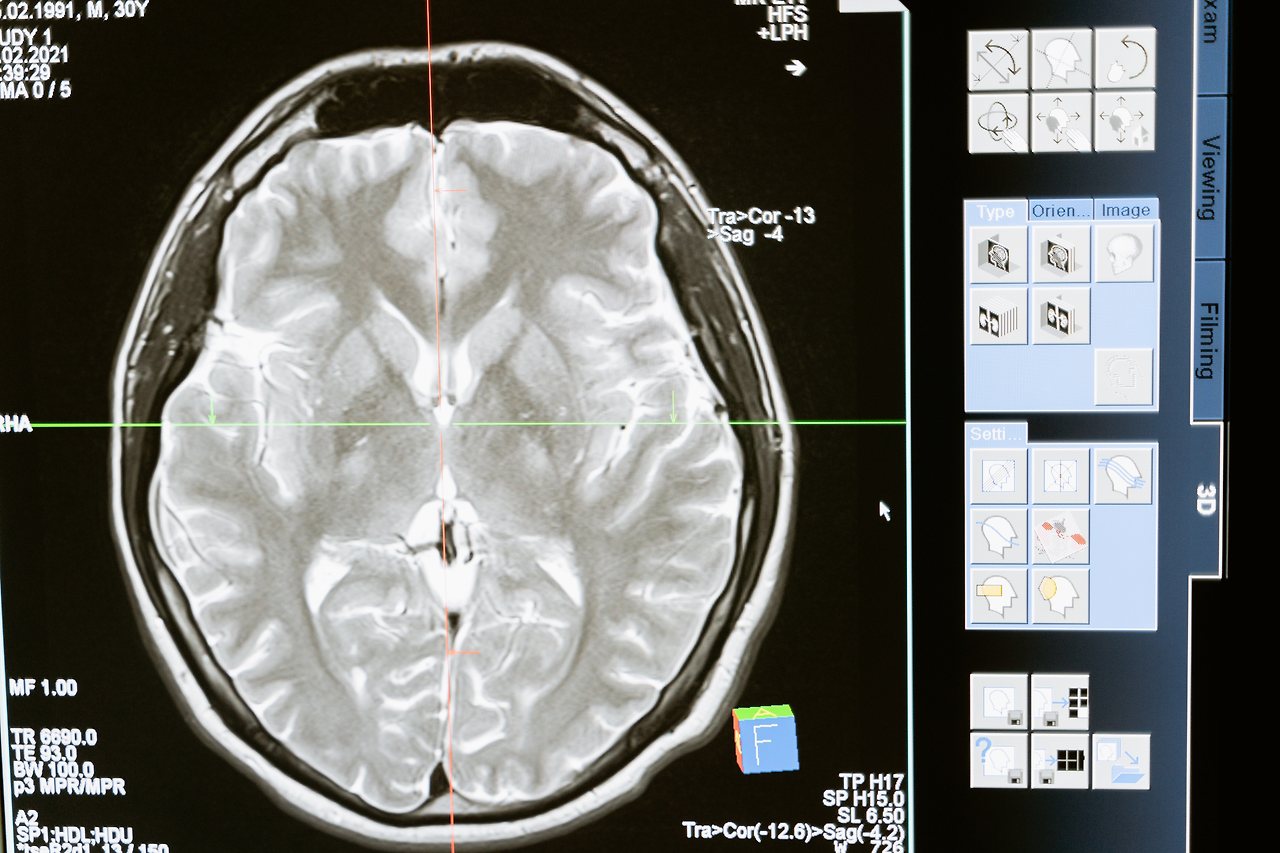

(뇌가 받아들인 그간의 정보가 많아 아이들에 비해 정보를 듬성듬성 넘어가게 시켜버리는 겁니다.)

어린 뇌는 어떤 상황을 더 '깊게' 기억해 냅니다.

성인기때까지 쌓아온 정보들이 많기에 뉴런이 정보를

더이상 받아들이지 않고, 뇌가 그렇게 지시 한다는 것입니다.

뇌에 연결된 수많은 뉴런들은 몸의 신경계에 연결되어 있습니다.

뇌가 퇴화되어가면, 몸의 근육 작용도 사실 받아들인 정보들이

많은 인간(어른)에게는 더이상 훈련하지 않아도 된다는 의식을

조금씩 지각시키는 단계입니다.

그래서 한 살 한 살 먹을 수록 몸이 더 무겁고 체력이 처지는 겁니다.